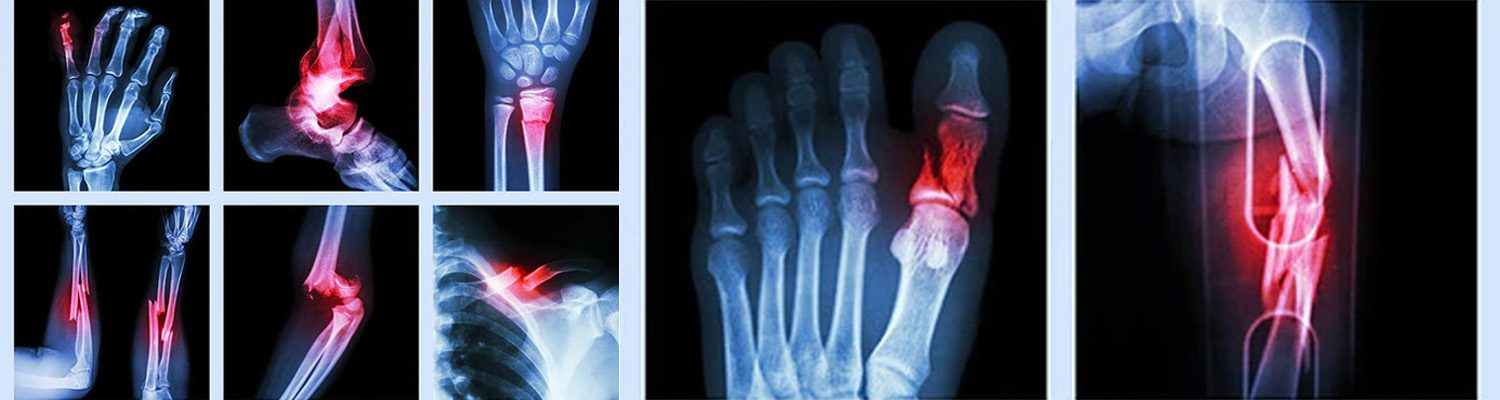

ফ্র্যাকচার (Fracture): হাড় ভাঙা সম্পর্কে জানুন বিস্তারিতভাবে

আমাদের দেহের প্রতিটি হাড় (bone) একটি গুরুত্বপূর্ণ কাঠামো তৈরি করে যা আমাদের চলাফেরা, ভারসাম্য এবং অঙ্গ-প্রত্যঙ্গের রক্ষা করে। কিন্তু দুর্ঘটনা, আঘাত বা অসুস্থতার কারণে কখনো কখনো এই হাড় ভেঙে যেতে পারে—এটাই ফ্র্যাকচার।

ফ্র্যাকচার (Fracture) হচ্ছে হাড়ে ফাটল, ভাঙন বা সম্পূর্ণ বিভাজন। এটি একটি সাধারণ অথচ গুরুত্বপূর্ণ হাড় সংক্রান্ত আঘাত, যা ছোট খাটো থেকে শুরু করে জটিল ও জীবনঘাতী হতে পারে। শিশু, বয়স্ক মানুষ এবং খেলোয়াড়দের মাঝে ফ্র্যাকচারের ঝুঁকি বেশি থাকে।

ফ্র্যাকচারের ধরণ (Types of Fracture):

ফ্র্যাকচার বিভিন্ন রকম হতে পারে, যা হাড়ের অবস্থান, ভাঙার ধরন ও গুরুতরতা অনুযায়ী ভাগ করা হয়। নিচে কিছু সাধারণ প্রকারভেদ দেওয়া হলো:

• X-ray বা MRI করে হাড়ের অবস্থা নির্ণয়